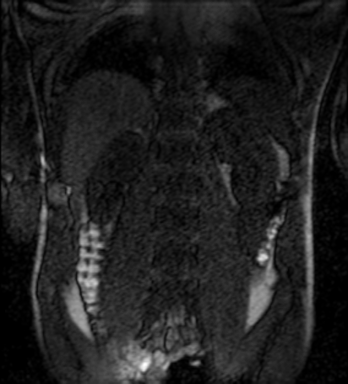

Tables 1 and 2 show our quantitative results: PSNR between the style (image we want to transfer style from) and generated image, SSIM and MS-SSIM between the content (image we want to take structure from) and generated image and finally, our proposed weighted SSIMs. For each style transfer direction and metric, our method consistently outperforms the other approaches. Figures 2 and 3 qualitatively highlight the good results of our method on 2D and 3D datasets. In addition, quantitative results on both figures show that our proposed metric preserves qualitative ordering of results for both style and content. In comparison, metrics such as SSIM struggle to accurately correlate to visual results.

Qualitative evaluation shows that the proposed method leads to sharper images, better content preservation, better localised CE and realistic MRI appearance. Quantitatively, we outperform the other algorithms with each metric, for each style transfer direction. While we expected that adding CE to images would be an easier task than removing CE, we found that for both tasks the method exhibits similarly performing quantitative and qualitative results. The results for style transfer with the kidney data show that when there is clear CE, it is easier to perform style transfer in both directions. However, when style transfer is performed on the prostate data, the model struggles in comparison to the kidney data. This may be due to the enhancement of the prostate being less defined than the kidney data. In figure 3(b), we can see the prostate with CE. Compared to figure 2(b) showing kidneys with CE, it is harder to determine the edges. The two original images shown in figures 3(a) and 3(b) are clear and easy to see some edges of prostate, in other images, it is harder to see the edges of the prostate.